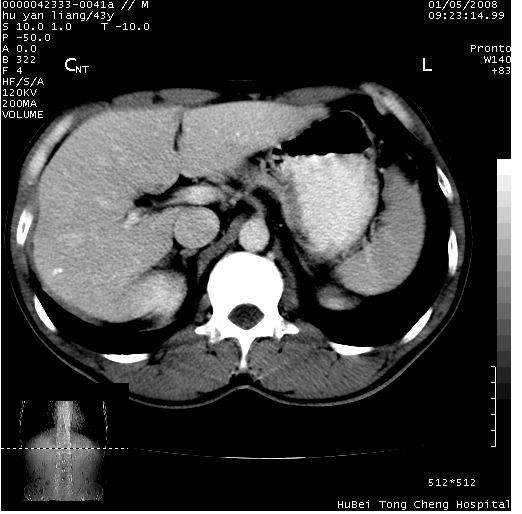

患者 男,43岁。右上腹不适1年余。既往有“肝右叶肝脓肿”病史,经保守治疗后痊愈。

b超提示:1)肝右叶肝内胆管结石。2)肝右叶占位性病变待排。

上中腹部ct轴位平扫+增强扫描(层厚10mm,螺距1.0,重建间隔10mm),图像如下:

肝右上叶偏后方较大团片状钙化灶,支持:肝脓肿后遗改变!

肝右叶后段团块状钙化灶,结合病史考虑肝脓肿痊愈后表现。